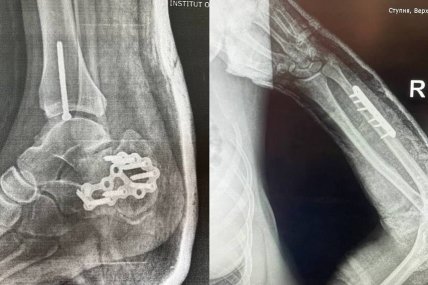

У прифронтовій зоні п’яний чоловік нібито збив бійців батальйону "Айдар", внаслідок чого вони зазнали тяжких поранень. Інцидент стався під час комендантської години.

"Як розповідають самі захисники, сталася ДТП ще й під час комендантської години. Військові отримали тяжкі травми, проте водій досі має посвідчення водія і продовжує їздити на авто", — йдеться в публікації.